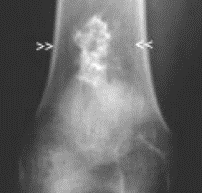

22

Q

Pathology?

A

Chondroblastoma

highly cellular, sheets of round to polygonal cells; multiple small foci of immature bluish-pink chondroid give a lobular appearance; multinucleated giant cells; chicken-wire (right photo) calcification